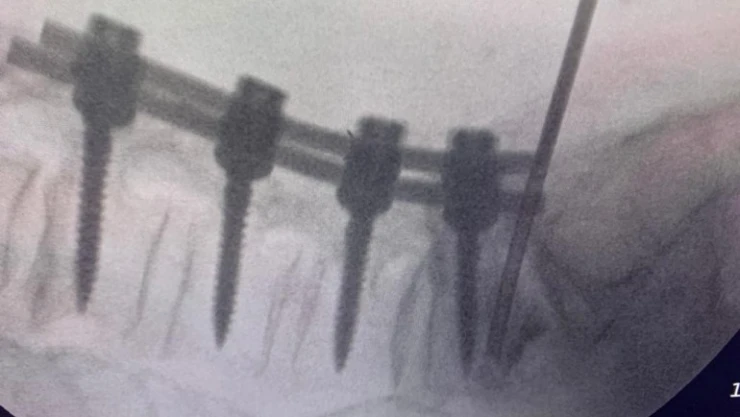

Beyin ve Sinir Cerrahisi Uzmanı Prof. Dr. Kemal Yücesoy, kırılmış vidalı kemiğe vidayı çıkarmadan kapalı yöntemle girerek müdahalede bulunmayı başardı. Açık ameliyata girmelerine gerek kalmayan hastalar, 5 dakikalık bir işlemle sağlıklarına kavuşurken, Prof. Dr. Kemal Yücesoy’un bulduğu bu yöntem dünya tıp literatürüne girdi.

Beyin ve Sinir Cerrahisi Uzmanı Prof. Dr. Kemal Yücesoy, vidalı omurganın kırığına dünyada ilk kez transforaminal transdiskal yaklaşımla sement desteği yaptı. Geliştirdiği yöntem, nöroşirürji alanında dünyanın en prestijli dergilerinden olan World Neurosurgery'nin son sayısında yayımlanarak literatüre girdi. Hastaların sadece 5 dakikasını alan ve 2 saat sonra günlük hayatına dönmesini sağlayan yöntem, Türkiye’ye gurur yaşattı.

Bu yöntemde, hastaya lokal anestezi uyguluyoruz. Kıkırdağın olduğu bölümden diskin içine iğneyle girip oradan da kemiğin içine ulaşıyoruz ve çimentoyu koyuyoruz. Bu daha önce hiç uygulanmamış bir yol. Kırılmış vidalı bir kemiğe ilk kez o vidayı çıkarmadan kapalı yöntemle girip müdahale etmiş olduk” diye konuştu.